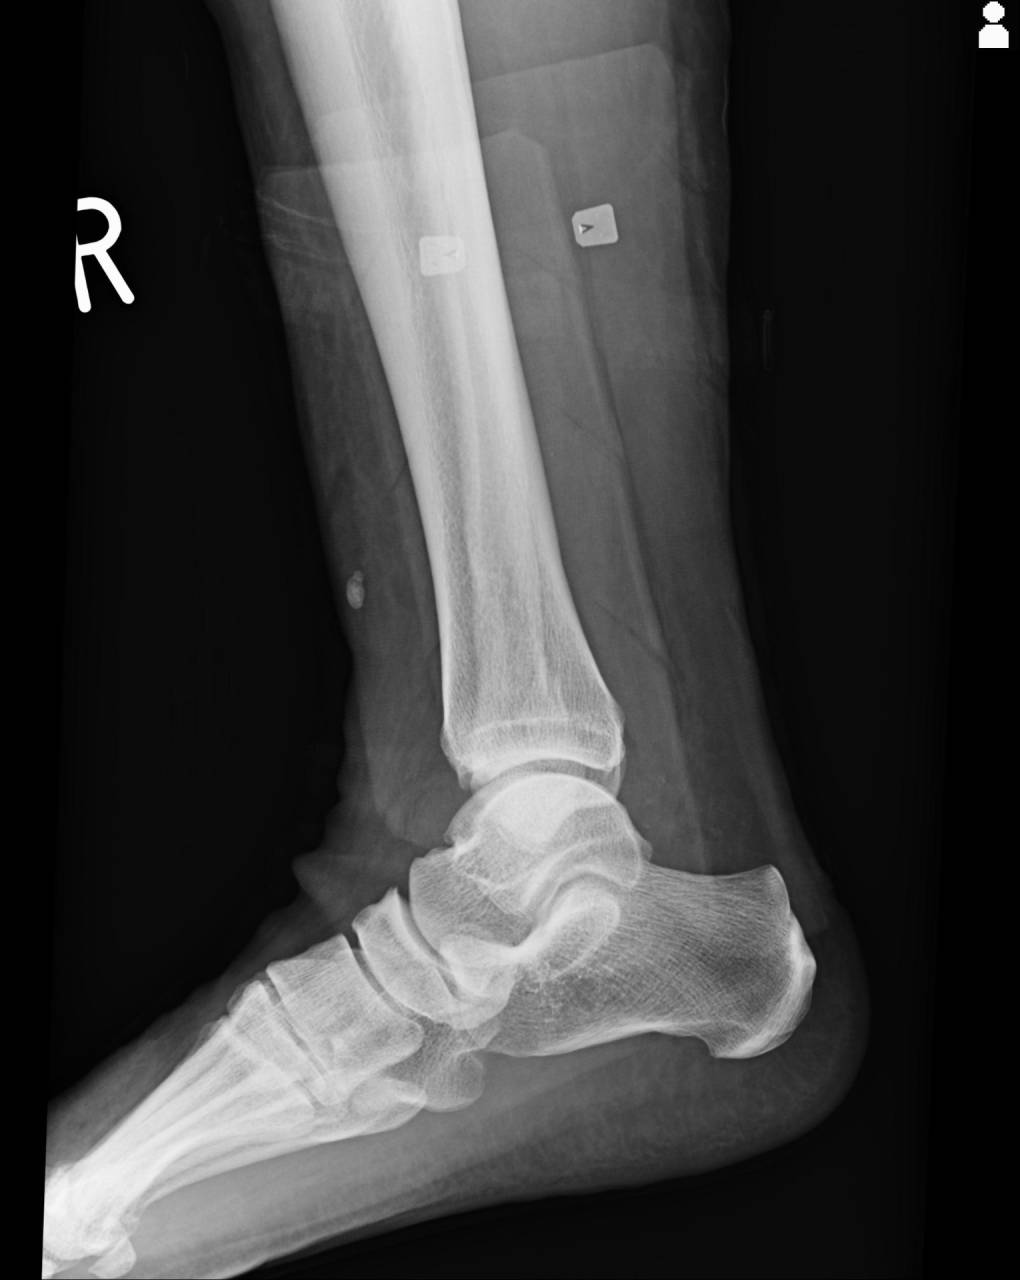

骨折の疑いが強いため、当整骨院が提携している病院にてレントゲン検査を依頼しました。

撮影した画像を確認すると外果部にエコーと徒手検査で怪しかった部位に骨折があり、若干の転位もありました。

腓骨の外果骨折として施術を進めていきます。